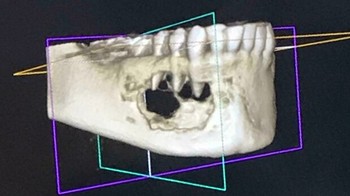

Foto scan CT memperlihatkan kondisi rahang yang dimakan tumor. Foto: Boredpanda